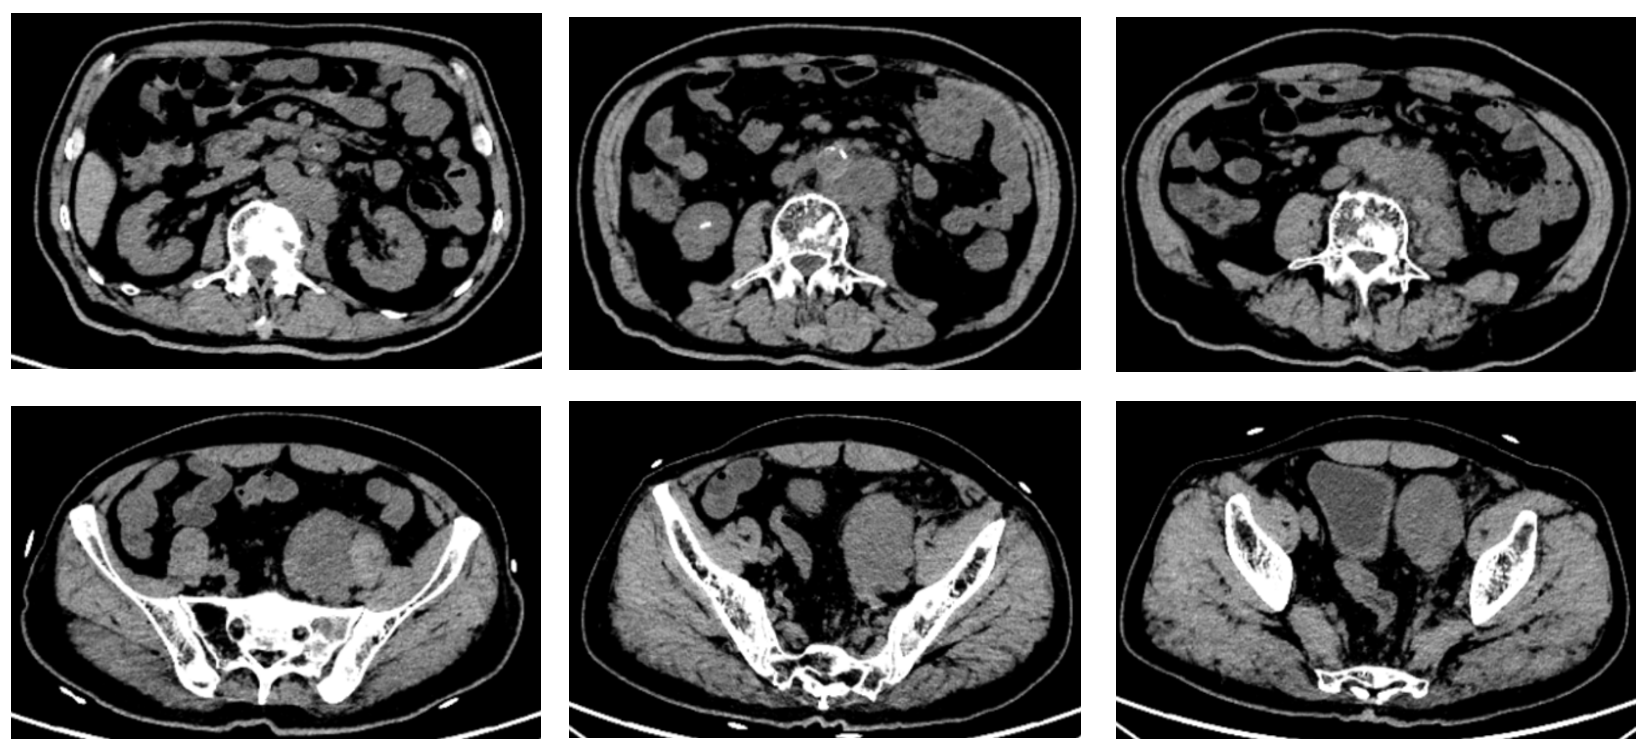

患者一月余前检查时发现右肾肿瘤,伴有肉眼血尿,尿频,尿急,尿痛,伴有腰痛,无发热等其他特殊不适,于当地医院超声检查提示右肾占位性病变,考虑肿瘤,为求进一步诊治于我院就诊,行肾脏增强CT检查提示右肾肿瘤,考虑肾透明细胞癌可能性大,肿瘤突破被膜,肾周受侵。病程中饮食睡眠欠佳,体重减轻近10kg。

右肾肿瘤 9.8cm*7.9cm

肾周受侵

肾门可见肿大淋巴结

未见明显远处转移

右肾肿瘤(肾透明细胞癌可能极大)III期 T3NxM0 IMDC 中危组。